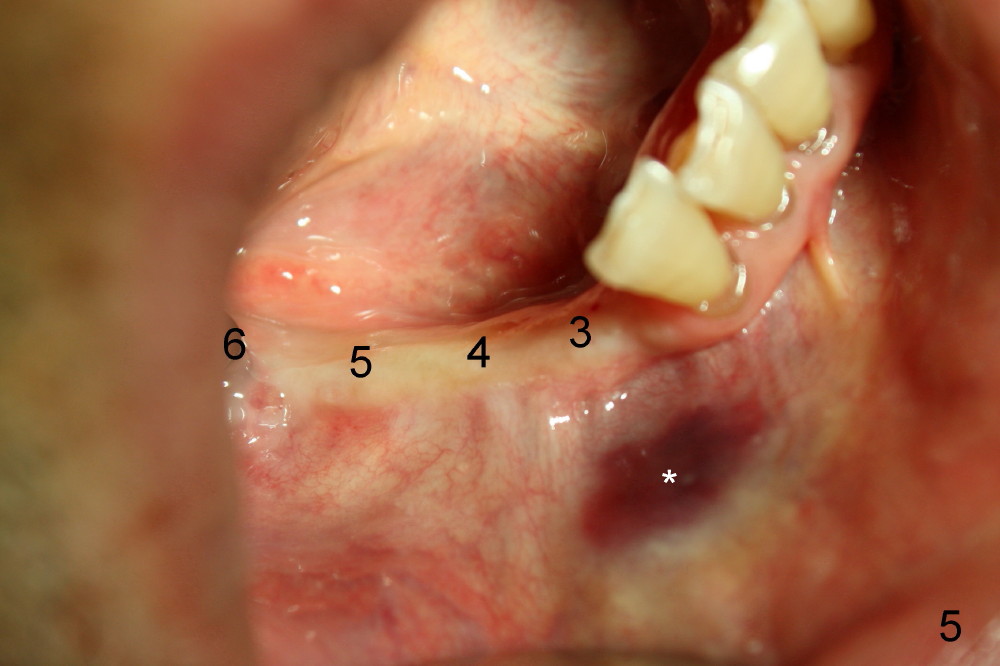

Several months ago, Philip (77 years old) was receiving chemotherapy for bladder cancer.  His lower right bridge broke down (Fig.1,2: #3-6: from canine to first molar).  The two abutment teeth (#3, 6) are nonsalvageable (Fig.4).  Ideally, immediate implant should be placed and implant-supported bridge is to be made.  The ridge at the site of #4 and 5 (premolars) is narrow.

Four months later, he returns and asks for implant restoration.  The ridge at the site of #3 is quite narrow (Fig.5).  While the socket of #3 is radiolucent (Fig.3 * under #3), there is an periapical abscess of the neighboring tooth (separate *).  It appears unsafe to place an implant at the site of #3, although anesthetic has been injected (Fig.5 *).  Instead an implant is placed at the site of #6 (5x14), further away from the infection.